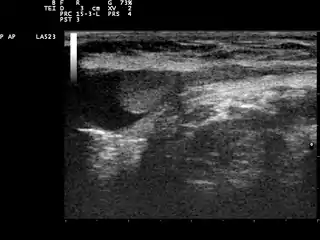

Se indica si un caballo es criptorquido al no sentir uno o ambos testículos en el escroto y se complementa con una ecografia hacia la región inguinal y región abdominal para buscar la ubicación del testículo o testículos no descendidos. En algunos casos, también se ayuda al diagnostico del caballo criptorquido a través de la palpación rectal pero no todos los machos se dejan hacer esta prueba diagnostica.